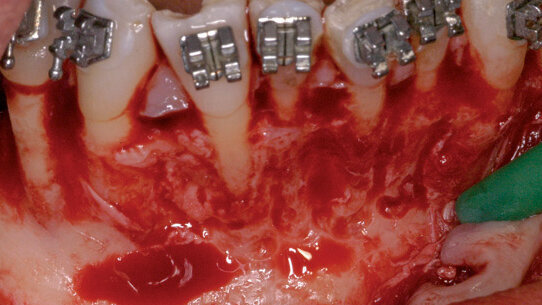

Con questa tecnica può ridurre significativamente il tempo totale di trattamento della terapia ortodontica. Limitarsi però a considerare solo la rapidità del trattamento è estremamente riduttivo, quando parliamo di questa tecnica. Ben altre possono essere infatti le indicazioni e i benefici di quella normalmente conosciuta come corticotomia.

Questo tecnica è relativamente nuova e richiede un ben coordinato approccio multidisciplinare. Alla base della tecnica c’è un intenzionale insulto chirurgico del tessuto osseo per provocare un iniziale stimolo infiammatorio che andrà a scatenare una serie di fenomeni a cascata, meglio descritti con l’acronimo di RAP (Regional Accelerated Phenomena1,2.

Il risultato del RAP è una transitoria osteopenia (diminuzione della mineralizzazione dell’osso senza perdita di volume), localizzata alla zona dell’insulto chirurgico. Il risultato clinico è un osso più morbido, che può consentire un più rapido movimento dei denti3,4, con minori stress per i tessuti parodontali. Un recente studio su casi estrattivi con radiografia tridemesionale pre e post operatoria ha evidenziato un incidenza dell’87 % di un riassorbimento di almeno 2 mm delle pareti alveolari.

Il movimento ortodontico parodontalmente accelerato, come descritto da Wilcko, viene definito “osteogenico” perché permette di creare osso ed espandere le basi alveolari. Ne consegue che le indicazioni pincipali sono: possibilità di espandere le basi ossee ed evitare molte estrazioni e rigenerare o irrobustire il parodonto. Appare quindi particolarmente indicato nei casi multidisciplinari per i quali è richiesto sia un movimento ortodontico che un intervento di chirurgia orale o parodontale. In questi casi, la corticotomia può essere combinata all'estrazione del dente di giudizio e / o una tecnica rigenerativa, come per esempio un aumento di cresta con innesto osseo, al fine di evitare interventi chirurgici multipli6-12.